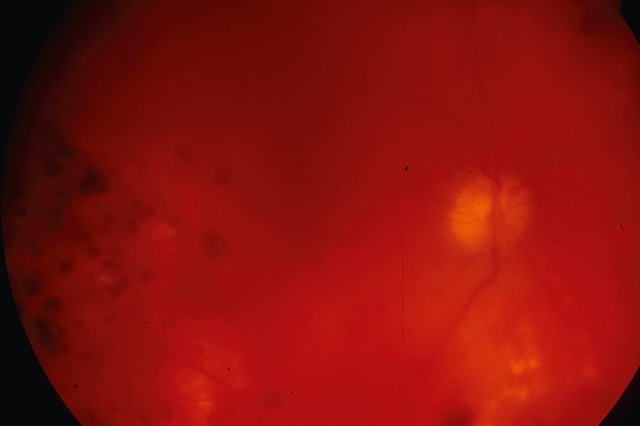

La cause de l’hémorragie est facile à reconnaître quand la rétine reste visible; ailleurs, une hémorragie massive rend la rétine invisible à l’examen du fond d’œil (fig. 8.5) : l’échographie B peut alors parfois orienter vers une étiologie (par exemple mise en évidence d’une déchirure rétinienne).

La rétine est masquée par l’hémorragie intravitréenne, et on ne perçoit plus que la papille et quelques cicatrices de laser dans le secteur temporal (bord gauche du cliché).

Image de fond d’œil en rétinographie couleur montrant une hémorragie intravitréenne de l’œil droit. La visualisation est globalement altérée par un voile rougeâtre diffus, typique d’un saignement dans le vitré, masquant partiellement les structures rétiniennes sous-jacentes. Malgré cette opacification, on distingue faiblement le nerf optique en temporal supérieur, à peine émergent dans l’ombre hémorragique, ainsi que quelques foyers plus denses d’exsudats jaunes dans la périphérie inférieure, suggérant un terrain pathologique chronique. De multiples taches sombres floues, dispersées dans le champ rétinien, correspondent à des amas de sang en suspension dans le corps vitré. Le flou visuel et la tonalité rouge globale de l’image sont caractéristiques d’un épisode aigu d’hémorragie intravitréenne, souvent en lien avec une rétinopathie diabétique proliférante ou une rupture vasculaire fragile. L’ambiance visuelle traduit bien la sévérité de l’épisode hémorragique et son impact fonctionnel immédiat.